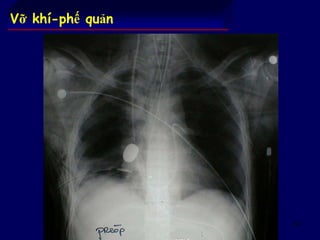

Vỡ khí-phế quản

Các dấu hiệu lâm sàng định hướng :

tràn khí dưới da (ở cổ sau khi đặt NKQ +++)

ho máu

Các dấu hiệu xquang :

tràn khí màng phổi (1/3 số trường hợp) còn tồn tại sau

dẫn lưu màng phổi

tràn khí trung thất

tràn khí màng phổi hoàn toàn & phổi xẹp xuống đáy ngực

Soi phế quản

có lẽ phải làm hệ thống

đôi khi lúc đầu âm tính (phù, tổn thương thành ngực)

có thể cho phép điều trị tạm thời tổn thương